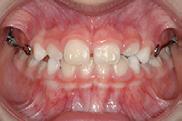

Initiation of treatment was judiciously delayed for several months (age 7), until both of the maxillary central incisors erupted sufficiently for fixed appliance fabrication. Expansion of the maxilla began immediately by turning the device 1/4 turn every other day. Initial expansion of 5mm was accomplished in 6 weeks. The expander was tied off with a steel ligature to prevent any change but permit further expansion as needed. A reverse pull facemask was delivered at this time. 1/2”, 14 oz. elastics were provided for traction between the hooks of the appliance and the facemask. These initial elastics generated approximately 350 grams of force. The patient was instructed to wear the facemask all the time except at school. PROGRESS photographs (Figure 5) were obtained one month later, and the elastic strength was increased to 5/16”, 14 oz., generating approximately 600 grams of force.

PROGRESS photographs (Figure 6) were again obtained six weeks later. They showed the development of a positive overjet. Over the next six months, wear time was gradually reduced to sleeping hours only. It was necessary to cut the expander arm to permit eruption of the maxillary right lateral incisor during this time.

Figure 5 - Appliance design courtesy of SSO Member Dr. Stuart Loos